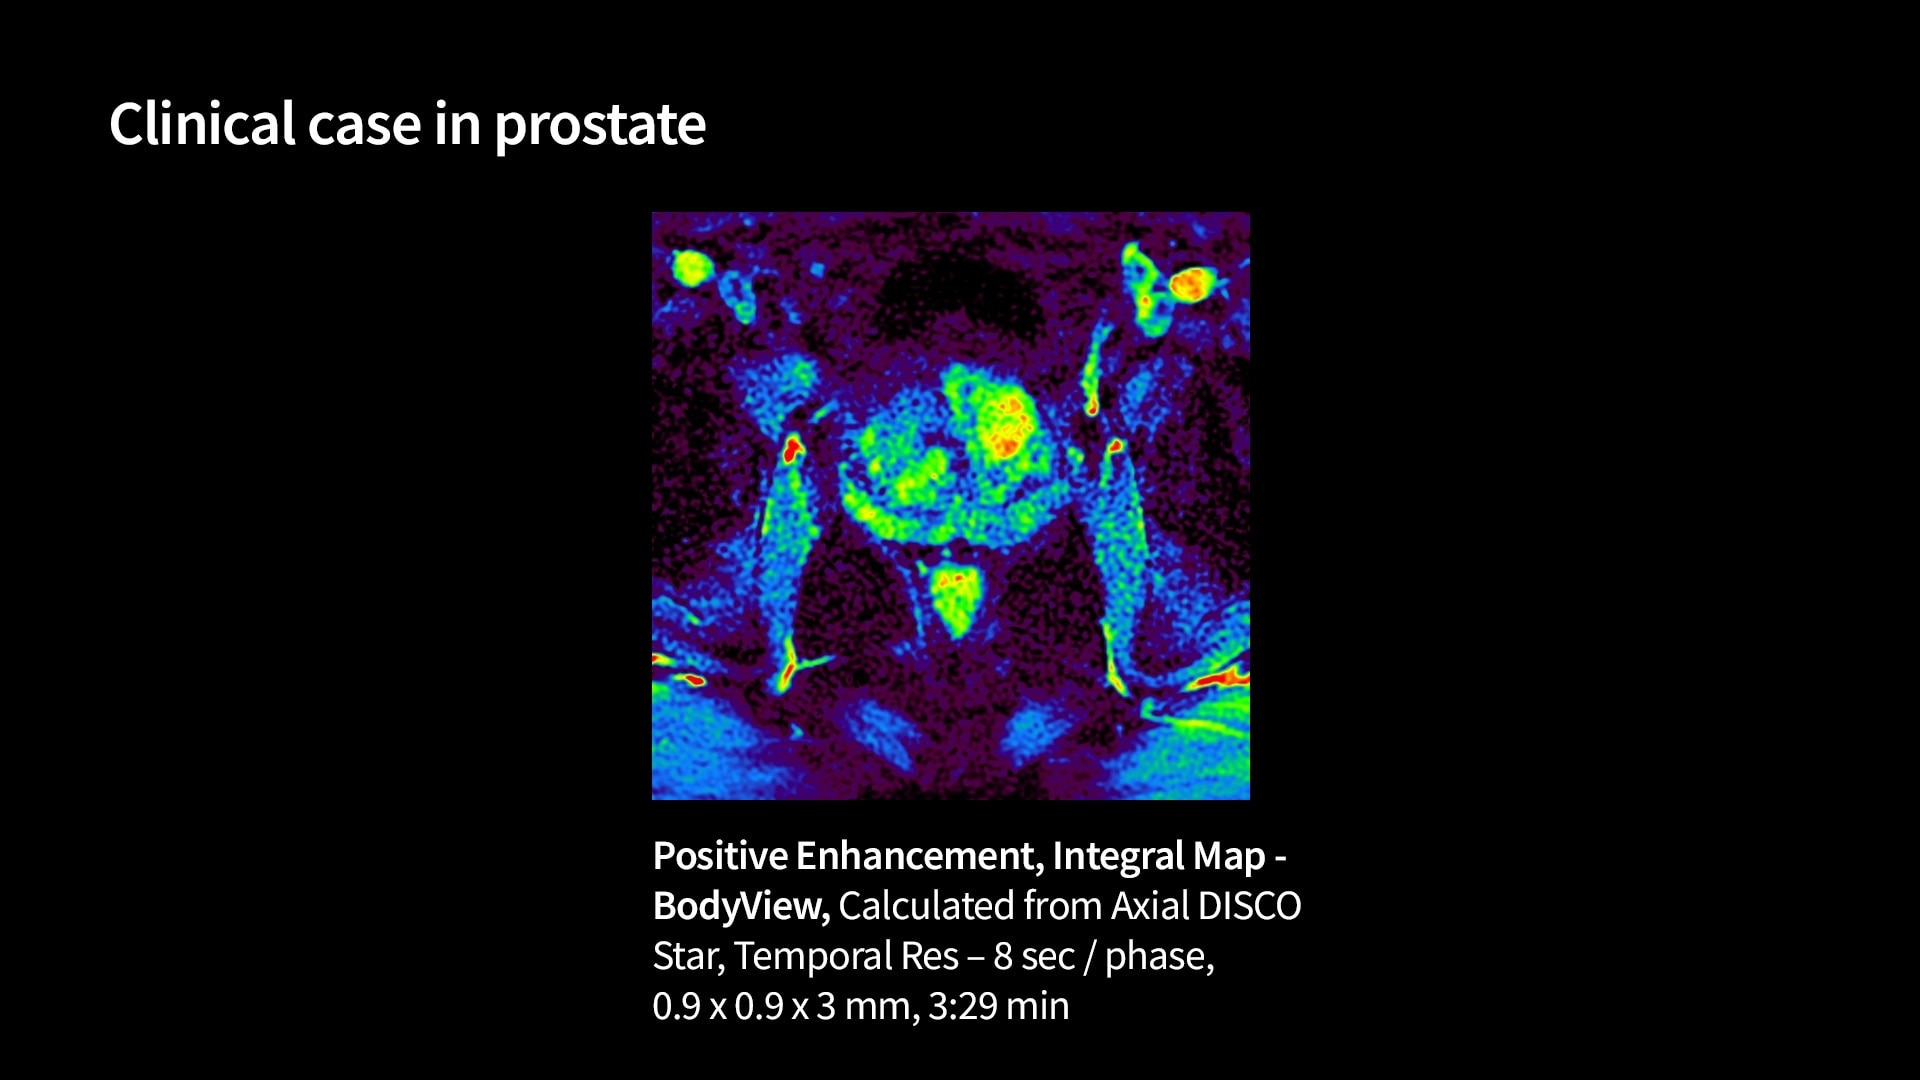

Quantifiable

Provides quantitative and actionable information